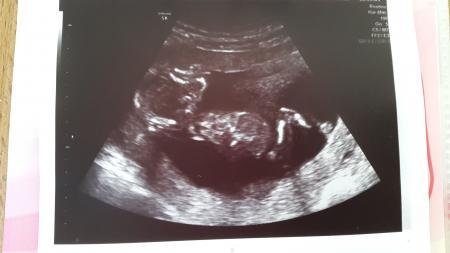

Gestern war ich wieder bei der FA. Es war der schönste Ultraschalltermin bisher! Man konnte so viel sehen. Erst hat sich das Baby am Knie gekratzt, das war das erste was wir sehen konnten! Die Hand war ganz deutlich! Atembewegungen hatte ich vorher noch nie im Ultraschall sehen können! Den Schädel mit Ober- und Unterkieferknochen. Und eh alle Knochen, Herz usw. Und wie es sich bewegt hat!

Ja, ein Foto haben wir auch. Ich lade es mal hoch. Bin jetzt mit den Handy hier, ich hoffe es geht!